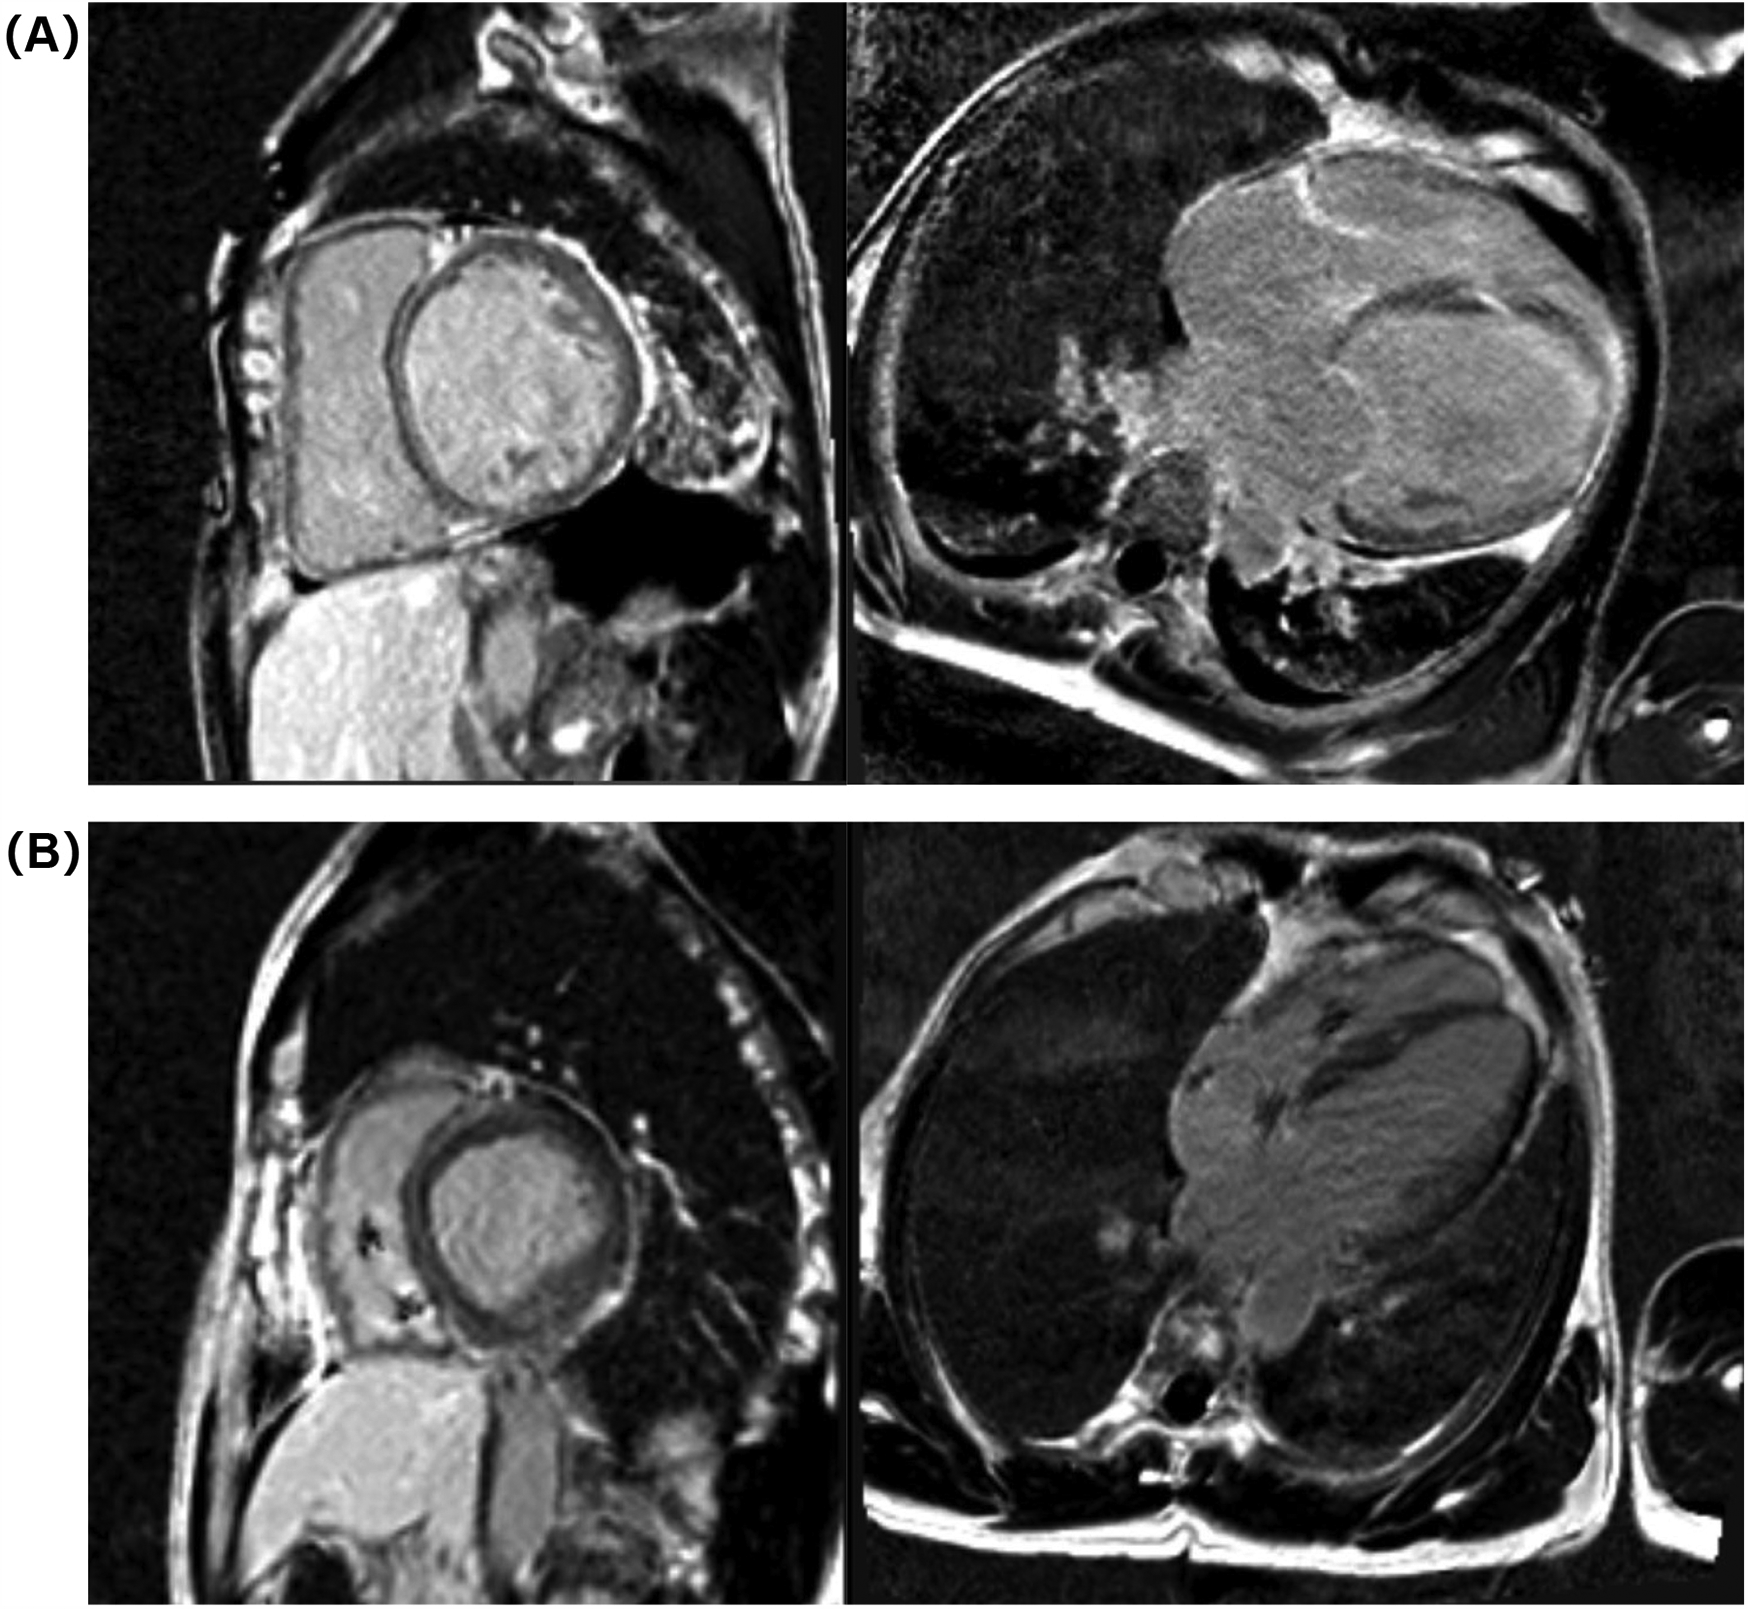

Electrocardiogram (ECG) on admission revealed sinus rhythm with a heart rate of 101 beats per minute and a QRS duration of 118 ms. 24-h Holter monitoring revealed sinus rhythm (average heart rate 89 beats per minute), 44 premature atrial contractions, and two episodes of short-duration atrial tachycardia. Continuous electrocardiogram and blood pressure monitoring device also did not show any evidence of atrial fibrillation. Echocardiography demonstrated global cardiac dilatation with both impaired left ventricular systolic and diastolic dysfunction, along with reduced right ventricular systolic. The LVEF was only 15% with an E/e’ ratio of 32.3, mtral inflow and tissue doppler imaging for diastolic function assessment are shown in Figures 1A–C. With moderate mitral regurgitation. Left ventricular wall motion was globally impaired. LV global longitudinal strain (GLS) was −3.3%. Although the patient was diagnosed with dilated cardiomyopathy (DCM), definitive supporting documentation was unavailable. Ancillary tests were performed to investigate the etiology of HF, with coronary angiography revealing no significant coronary artery abnormalities. Cardiac magnetic resonance imaging (MRI), both plain and contrast-enhanced, showed end-diastolic volume (EDV) of 288 ml, end-systolic volume (ESV) of 217 ml, stroke volume (SV) of 71 ml. MRI further revealed patchy fibrosis is observed in the mid-myocardial layer of the left ventricle and in the anterior and posterior walls at the junction of the left and right ventricles (Figure 2A). No fibrosis is noted in the interventricular septal myocardium, with the total fibrotic area comprising less than 50%. Based on these findings, the patient was diagnosed with DCM. Right heart catheterization (RHC) revealed a CO of 1.93 L/min, a mean pulmonary artery pressure (mPAP) of 42 mmHg, a pulmonary capillary wedge pressure (PCWP) of 30 mmHg, and a pulmonary vascular resistance of 6.21 WU.

Figure 2

Cardiac MRI images at admission (A) and 1-year follow-up (B).

At the 6-month follow-up, GDMT was titrated as follows: sacubitril/valsartan 200 mg twice daily, metoprolol succinate 47.5 mg once daily, empagliflozin 10 mg once daily, and spironolactone 20 mg once daily. A 12-month follow-up cardiac MRI showed no significant changes in the location or extent of fibrosis compared to pre-treatment findings (Figure 2B). The GDMT optimization protocol and corresponding parameter adjustments during follow-up were shown in Figure 4.